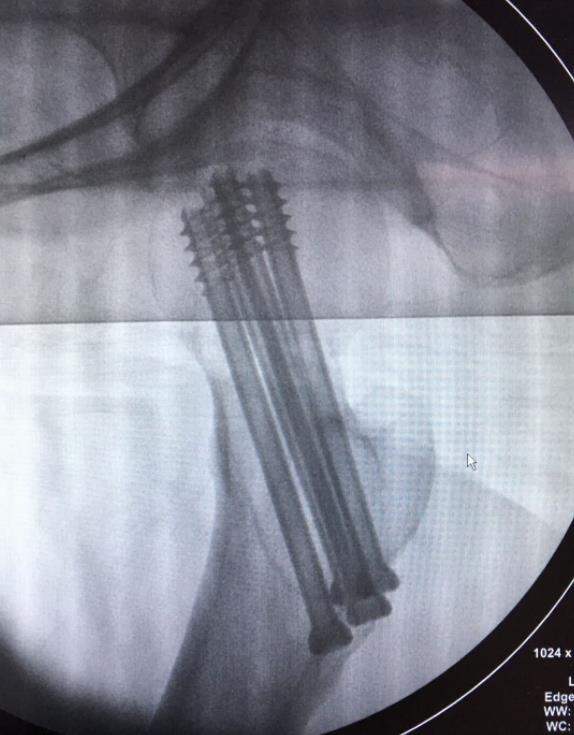

1、经皮沿股骨颈轴线置入空心钉导针,确保导针平行;

2、标准放置螺钉为倒三角形,其中下方螺钉在股骨矩,后方螺钉在后方骨皮质、研究发现倒三角形平行三枚螺钉能提供最佳的固定强度;

4、两个平面透视导针位置良好后切开皮肤,空心钻铭孔,导针引导下拧入空心钉,空心钉确保所有螺纹位于骨折线近端,螺钉头应距离软骨下骨5mm。

临床病例